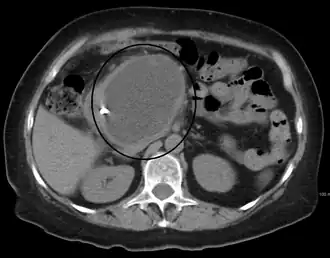

| A pancreatic pseudocyst as seen on CT | |

- Tomografia computadorizada[10]: Este é o padrão ouro para avaliação inicial e para o seguimento.